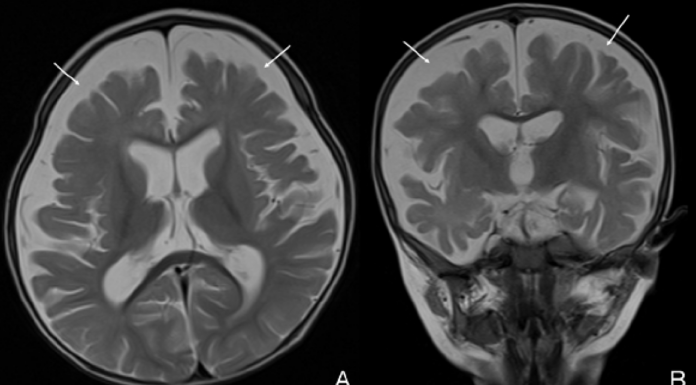

Možganska atrofija pri dojenčku vegetarijanske matere zaradi pomanjkanja vitamina B12

V razvitih državah se pomanjkanje vitamina B12 (kobalamina) običajno pojavi pri dojenih otrocih, katerih matere so vegetarijanke ali veganke, kar povzroči nizke zaloge vitamina...